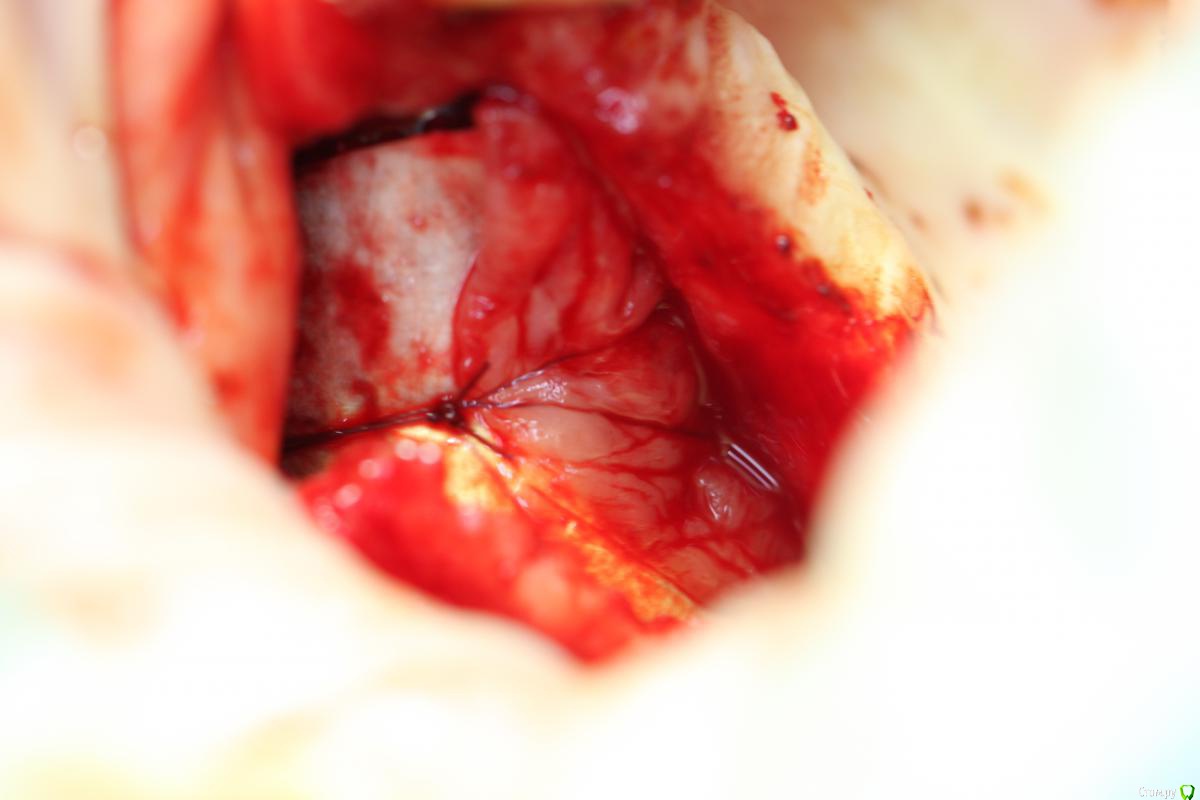

gum Опубликовано 17 января, 2017 Поделиться Опубликовано 17 января, 2017 Если остальная часть материала оссифицировалась, то может быть, раскрыть, вычистить не сформировавшийся материал, установить имплантат (фиксация апикально в сформированную кость) и добавить костный материал в пустоту и под мембрану и все, кортикалка со всех сторон сохранена, воспаления нет, через окно прозондируете плотность материала. Как думаете возможен такой вариант? 1 Ссылка на комментарий

kamranchick Опубликовано 17 января, 2017 Поделиться Опубликовано 17 января, 2017 Если остальная часть материала оссифицировалась, то может быть, раскрыть, вычистить не сформировавшийся материал, установить имплантат (фиксация апикально в сформированную кость) и добавить костный материал в пустоту и под мембрану и все, кортикалка со всех сторон сохранена, воспаления нет, через окно прозондируете плотность материала. Как думаете возможен такой вариант?с таким раскладом, ничего не надо будет засыпать, ибо сгусток будет и свое дело сделает. Ссылка на комментарий

Bier Опубликовано 17 января, 2017 Автор Поделиться Опубликовано 17 января, 2017 как думаете, почему не весь графт отработал? На установке болтов окно после синуса "окостенелое" было?потому что произошла неполная отслойка слизистой пазухи во время операции. Она подвернулась или расслоилась. 1 Ссылка на комментарий